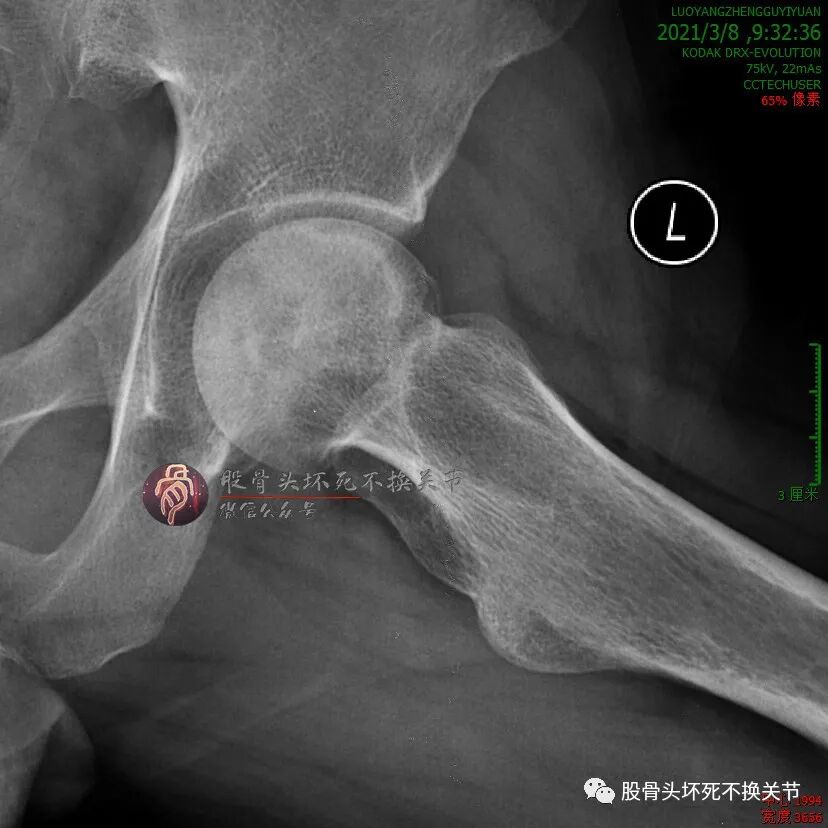

但是,疼痛缓解给予病人莫大希望,开始定期门诊治疗(不用住院、随治随走那种),半年后复查:

这次复查比初次就诊时明显好转,骨密度明显提高,疼痛基本全无,恢复一般的生活、工作能力。

继续定期门诊治疗,又过了5个月:

还行吧,骨密度就那样。